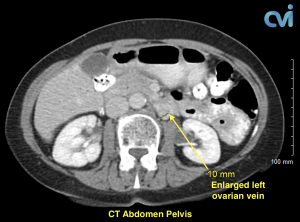

PCS can be diagnosed by Ultrasound or CT of the Abdomen and Pelvis.

Magnetic resonance imaging (MRI) and computed tomography (CT) is another method to diagnose pelvic congestion syndrome. Our practice requires a CT of the Abdomen and Pelvis with contrast prior to treatment. This allows us to see where the varicose veins are coming from so that we can plan and do the appropriate treatment. Sometimes there are abnormal pelvic veins in addition to the ovarian veins that need treatment. Sometimes PCS can be missed on CT if the contrast injection is not timed appropriately or the vein is not directly measured.

Our specialist who is also a Board Certified Radiologist will review all of your imaging personally to make sure an accurate diagnosis is made. Following an accurate diagnosis, you can then undergo the Ovarian Vein Embolization procedure.